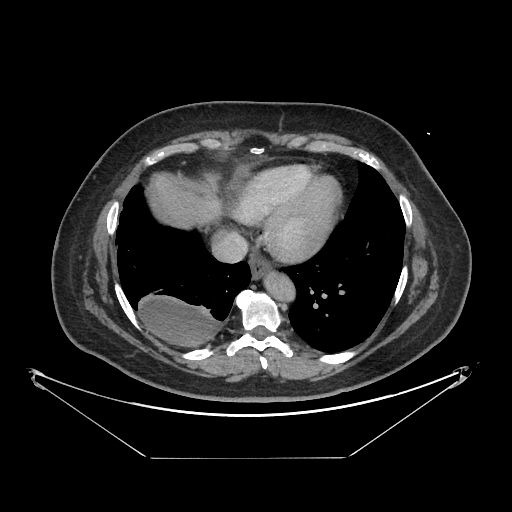

Image Grid

4×3 grid: Rows show different image types (Original NATIVE, Reconstructed NATIVE, Original VENOUS, Generated VENOUS), Columns show windowing techniques (No Window, Lung Window, Mediastinum Window)

Original VENOUS CT scan

No window - Raw intensity values

Original VENOUS CT scan

Lung window (WL -600, WW 1500 → Low −1350, High +150)

Original VENOUS CT scan

Mediastinum window (WL 40, WW 400 → Low −160, High +240)

Generated VENOUS CT scan (A→B translation)

No window - Raw intensity values

Generated VENOUS CT scan (A→B translation)

Lung window (WL -600, WW 1500 → Low −1350, High +150)

Generated VENOUS CT scan (A→B translation)

Mediastinum window (WL 40, WW 400 → Low −160, High +240)